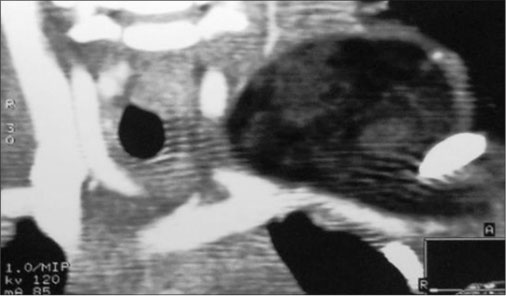

Ultrasound of the swelling revealed a heterogeneous mass at the base of posterior aspect of neck in midline with increased vascularity. On magnetic resonance imaging (MRI), a subcutaneous lesion was found superficial to the paravertebral muscles without any communication with the spinal cord. T1- and T2-weighted images showed increased peripheral vascularity. On T2 images, it was observed as a hypointense lesion [Figure 1].

|?Fig. 1: Magnetic resonance imaging showing posterior cervical lesion

Diagnostic imaging studies are invaluable in the preliminary diagnosis of fatty tumors.[2] Plain X-rays and computed tomography (CT) scan can suggest the fat density of the tumor. Results of ultrasonography examinations can be confusing. The MRI is the most reliable method showing location, size, extent, and mass characteristics of the tumor.[1] Hibernomas are usually depicted as heterogeneous masses with marked contrast enhancement. The CT and MRI examinations show a well-demarcated mass having signal intensity which is intermediate between subcutaneous fat and muscle. The lesion enhances after contrast injection. Despite presenting as brown fat, the T1- and T2-weighted images demonstrate high-signal intensity but slightly less than that of the subcutaneous fat. On fat-suppression sequences, there may be incomplete fat suppression because of the nature and amount of lipids.[6] [7] [11]

|?Fig. 1: Magnetic resonance imaging showing posterior cervical lesion